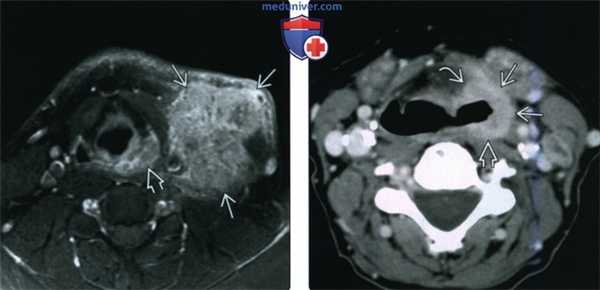

(Слева) Аксиальная КТ с КУ: опухоль, минимально накапливающая контраст, инфильтрирует черпаловидные хрящи и мягкие ткани вокруг них, но заглоточная жировая ткань В сзади визуализируется отчетливо. Сохранность заглоточной жировой клетчатки помогает отличить рак за перстневидной области от опухоли задней стенки гортаноглотки. Визуализируются измененные лимфатические узлы справа.

(Справа) При аксиальной КТ с КУ на более каудальном уровне определяется утолщение гортаноглотки и неравномерная деструкция перстневидного хряща с распространением опухоли в задние отделы гортани. Отмечается шейный лимфоузел справа. Эта опухоль представляет собой ПКР (T4aN2c).